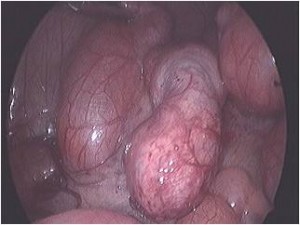

Acute scrotum is sudden onset of redness and swelling over the scrotum. This is associated with severe pain over the scrotum and sometimes lower abdomen and may be accompanied with nausea and vomiting.

Of the many causes of acute scrotum, the most common and important is Torsion of Testis. The testis is supplied by a single blood vessel and any torsion on this vessel may impede the blood supply to the testis. If urgent medical attention and intervention is not done, this may result in testicular gangrene and orchidectomy ( removal of the dead testis) may be needed.

The commonly misleading history given by the parents is that the child may have had a trivial trauma or an insect bite. However, for the clinician the golden rule should be ‘Any acute scrotum is testicular torsion unless proved otherwise’. Investigations like ultrasound and color doppler may be done to help in the diagnosis. However, in the event of any doubt, it is safest to do a surgical exploration of the scrotum. The other uncommon causes of acute scrotum are acute epidydymo orchitis, scrotal abscess, idiopathic scrotal oedema and torsion of appendix of the testis. ●

Acute Scrotum (Right scrotal Abscess)

Acute Scrotum